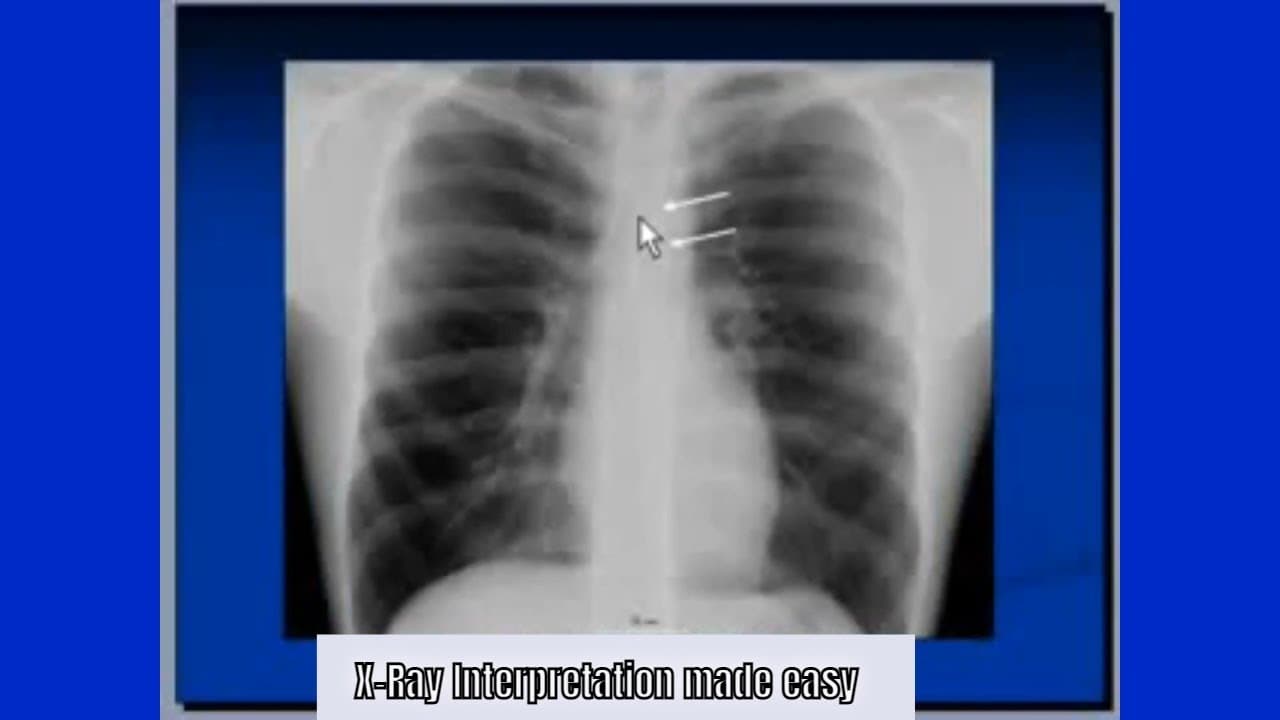

Chest X-Ray Interpretation: Step-by-Step Guide for Medical Professionals

In this video, we provide a comprehensive walkthrough on how to interpret a chest x-ray (CXR) using a clear and systematic approach. Whether you're a medical student, resident, nurse, or practicing physician, this tutorial will help sharpen your diagnostic skills in reading CXRs. You’ll learn how to: Identify normal and abnormal chest x-ray findings Recognize signs of lung collapse, pneumothorax, pleural effusion, and more Understand the ABCDE method of CXR interpretation Avoid common mista...